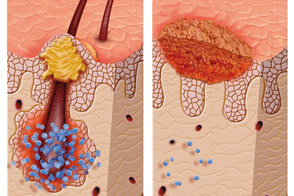

Inflammatory Phase: fibrin and insoluble proteins – essential part of the blood clots – are formed and connect to the exposed collagen to promote blood flow interruption – a process called hemostasis.

Inflammatory cells called neutrophils emerge in the early hours of the injury to annihilate the microbes, thus limiting the infection of the lesion. Subsequently, macrophages cells arrive to destroy the remaining microbes and help signal the proliferation of fibroblasts, the cells that are responsible for collagen formation.

2. Proliferative Phase: Fibroblasts are stimulated to synthesize collagen and form granulation tissue. This new tissue is fueled by the growth of new blood vessels through a process called angiogenesis.

3. Remodeling phase: This phase is characterized by the re-epithelialization that reconstructs the tissue. The new layer covers the injured skin and allows the repair process to continue. At this stage, the new tissue is put and practically restores the whole condition of the original tissue.

In chronic injuries, the healing process remains in the inflammatory phase for a long time or indefinitely. The immunocompetent cells, which are responsible not only for the coordination of cellular and biochemical events, but also for the resolution of wound healing, do not become fully functional and wildly release cytotoxic substances, which are normally used to fight pathogens and worsen of the lesion.